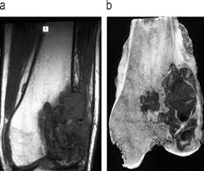

Se usa una amplia gama de técnicas de adquisición de imágenes para poder ver dentro del cuerpo y determinar el alcance de un sarcoma óseo y establecer la presencia o ausencia de enfermedad metastásica distante.

1. Rayos X

2. Resonancia magnética

3. TAC contrastado

4. Gammagrafía Ósea